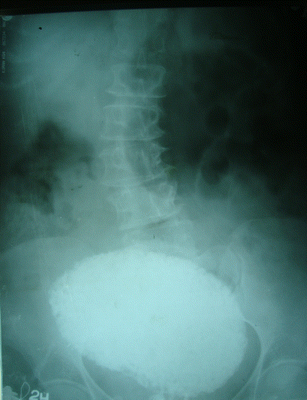

Mature ovarian dermoid cyst invading the urinary bladder ...

Mature ovarian dermoid cyst invading the urinary bladder ... from obgyn.onlinelibrary.wiley.com